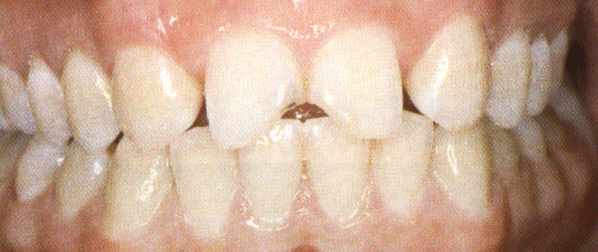

Tandbederf in de kies schemert als een donkere vlek door.

De kies drie jaar na het vullen met composiet.